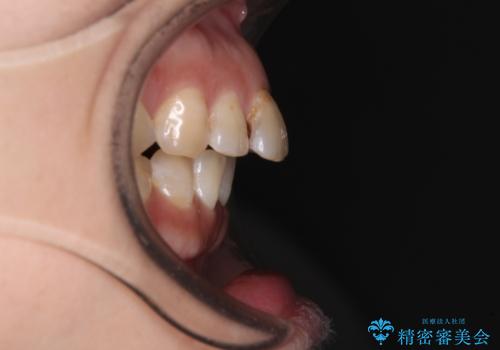

- 飛び出た上の前歯を気にして来院された患者様です。

奥歯の咬み合わせは、上顎歯列が理想的な一よりも数mm前方にある状態でした。